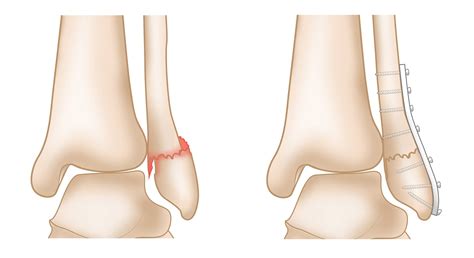

For more severe fractures, especially those involving displacement or multiple fragments, surgery may be necessary. Surgical options include:

• Open Reduction and Internal Fixation (ORIF): This procedure involves realigning the bone fragments and securing them with plates, screws, or rods.

• Arthroscopy: In some cases, minimally invasive arthroscopy may be used to repair the fracture and assess any associated damage to the joint.